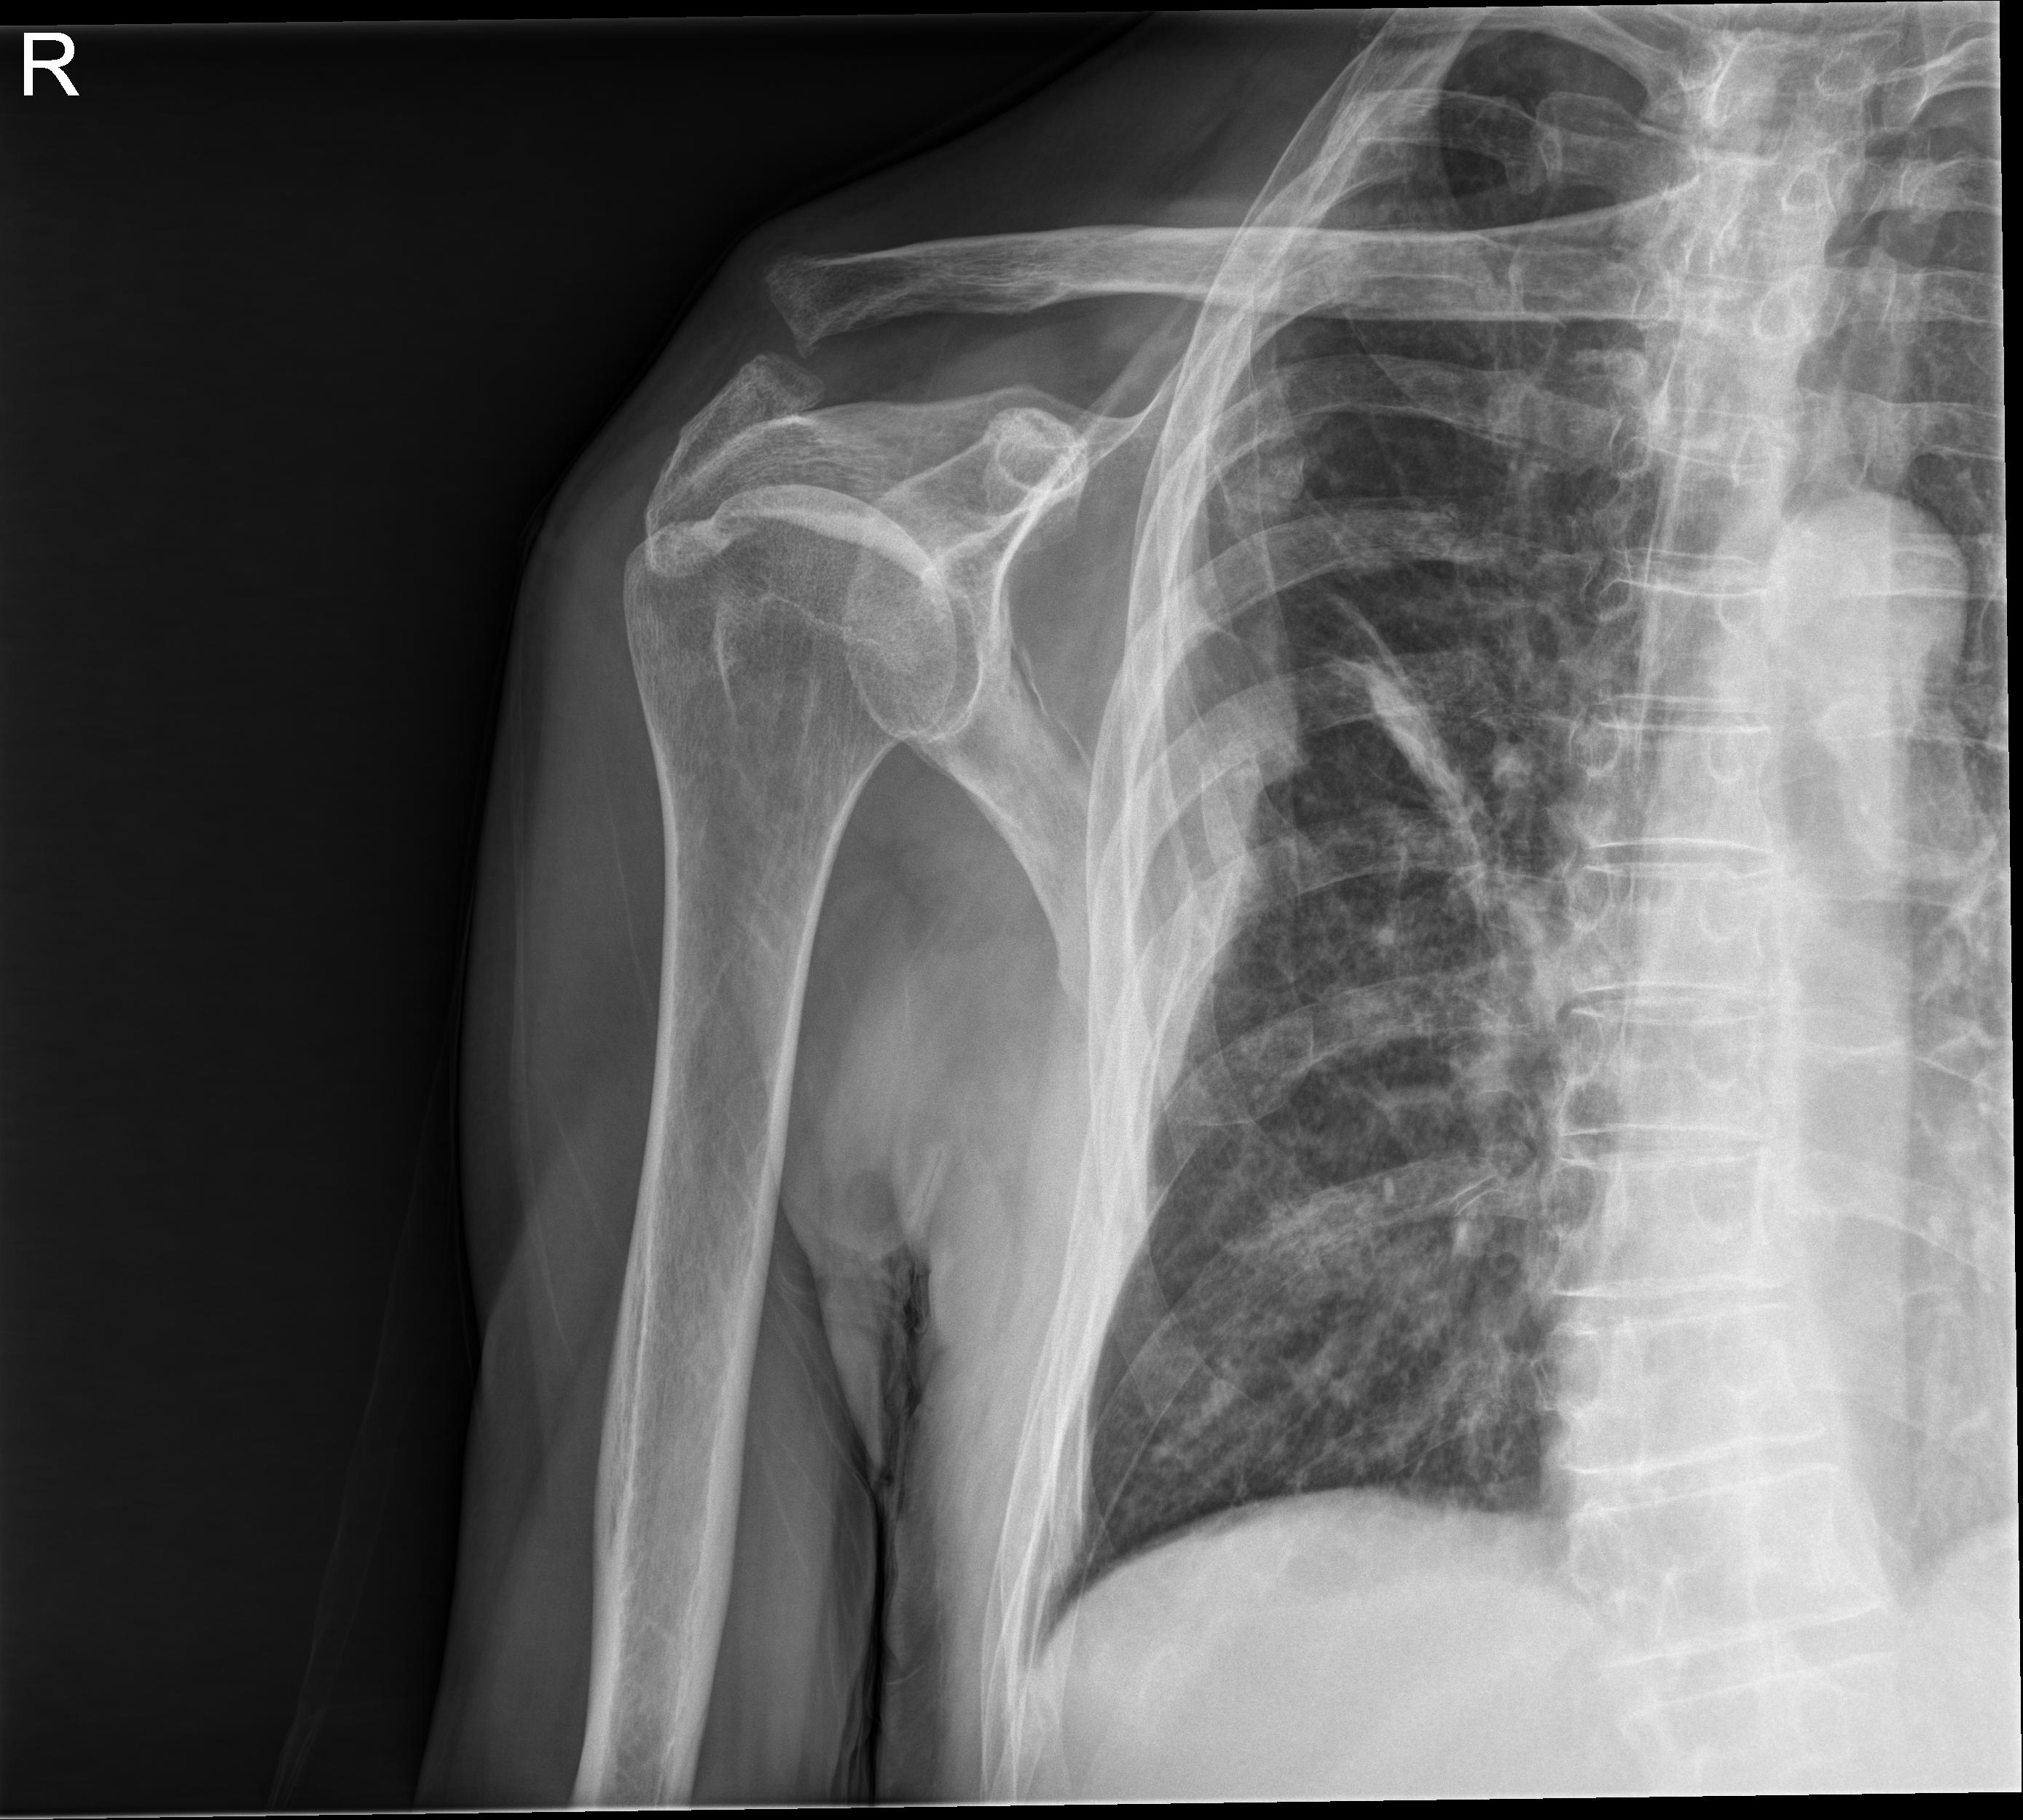

1 Hombro der.